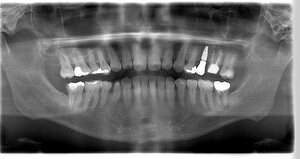

レントゲン写真

- 透過像

症例写真-1

- Befor

- After

症例写真-2

- 途中経過

| 年齢 | 50代・男性 |

|---|---|

| 主訴 | 右下歯が疼く |

| 治療内容 | ・右下6番インプラント ※1:FGG(遊離歯肉移植術)とは、足りない歯ぐきを上顎から上皮を切り取り移植する外科手術 |

| 治療費 | 合計:902,000円(税込) ■内訳 |

| 治療期間 | 9ヵ月 |

| 治療方針 | 右下の当該歯は歯根破折により保存不可能と診断しました。歯周疾患も伴っていたため抜歯後に骨吸収※1が大きく起こることが予測できました。チタンメッシュ併用骨再生誘導法(GBR※2)を選択しインプラント埋入と同時に行い自然な歯槽骨のラインを再現しました。またGBRを行う際にインプラント辺縁の付着歯肉の減少が起こる為、遊離歯肉移植術(FGG※3)を行い清掃性を考慮した形態に仕上げました。 ■治療方針の解説 治療した右下の歯をレントゲンで撮影したところ根本の部分に黒く写る箇所があり「根尖性慢性周囲炎※1」と診断。また歯周病も進行していました。 ※1 骨吸収・・・歯槽骨という歯を支える骨がなくなっていくこと |

| 担当者所見 | 主訴の右下だけでなく歯茎の腫れ、発赤があり不良補綴や不良充填など他にも治療箇所が多数ありました。プラークコントロールが不良であった為まずはブラッシング指導を行いセルフケアの重要性を理解していただくところからスタートしました。 右下6番の歯はインプラント治療を行なった結果審美的にも機能的にも患者様の満足を得ることができました。骨造成と歯肉移植も行なった為インプラントを支える十分な歯周組織の獲得ができたと思っております。 |